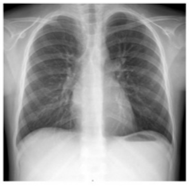

Case Report

Hypersensitivity Pneumonitis, a Rare Diagnosis in a Paediatric Patient

Joana Ferreira Mendes, Sara Sofia S Rodrigues, Inês Araújo Oliveira, Joana Monteiro and Joana Cardoso. 13(7): 01-05.